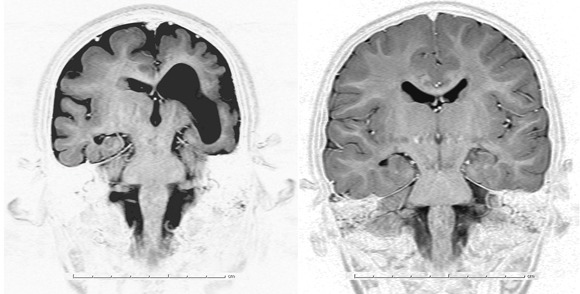

Whole exome DNA sequencing is one of the NextGen technologies that are being applied to neurologic disorders. Unlike whole genome sequencing, whole exome DNA sequencing focuses on the small portion of the genome (less than 2%) that contains protein-coding bits of DNA, known as the exome. For example, Dr. Murat Gunel, chief of the Neurovascular Surgery Program and codirector of the Program on Neurogenetics at Yale University, New Haven, Conn., recently used whole exome sequencing to determine that several distinct types of malformations of cortical development, including microcephaly, pachygyria with cortical thickening, and hypoplasia of the corpus callosum were all associated with recessive mutations in a single gene, WDR62 (Nature 2010;467:207-10). This discovery was made by analyzing the DNA of several children with microcephaly among 30 interrelated Turkish families.